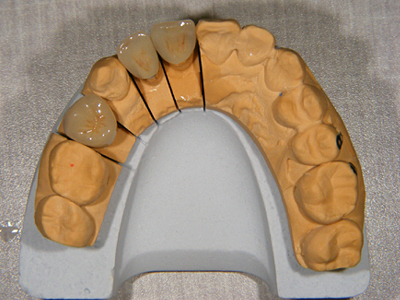

12. 作成模型

右上1,2,4番(3番以外)の歯冠を作成するための精密模型です。以前より入っていた不適合の冠2,4番と根管充填のままの1番です。患者様は歯列改善に対して喜んで下さり、セラミック冠(MB冠、自費でまたやっていただけました。1歯11万5500円、14Kコア別途)で作成することになりました。患者様の医療不信は解けましたが、信頼に応えるための責任の重さを強く感じます。